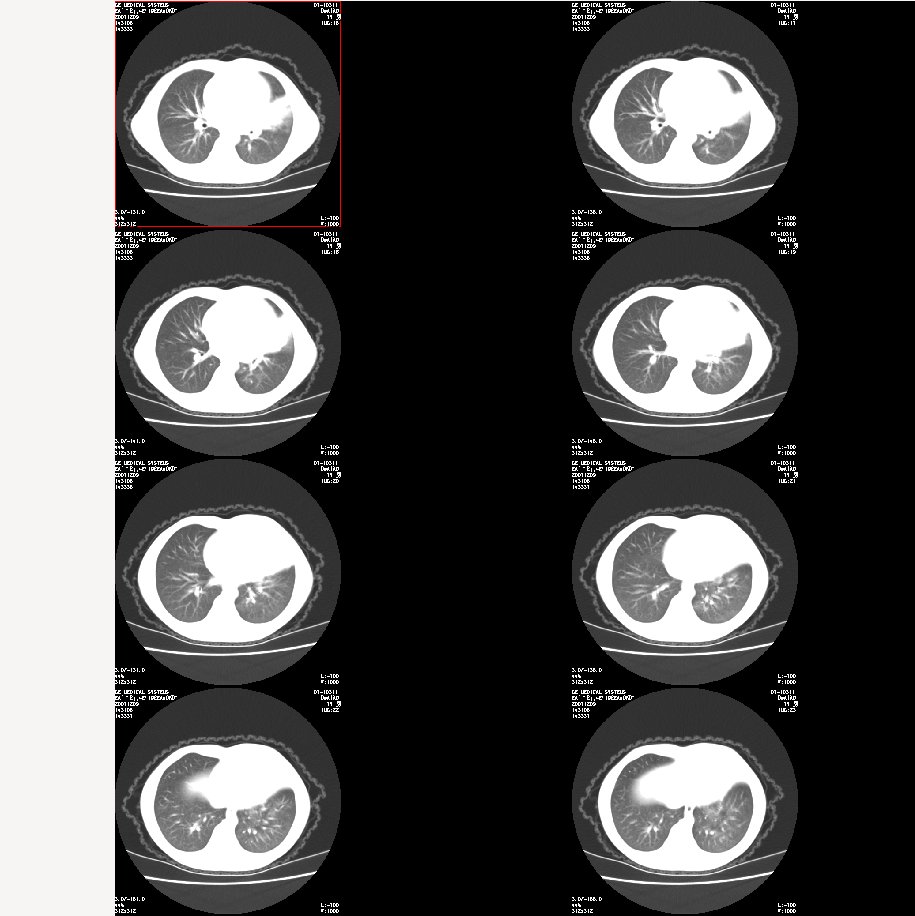

m 7

咳嗽、咯血半月。查体:双肺呼吸音粗,可及干湿鸣。自诉每年均有发作。

肺窗: